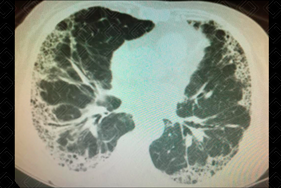

Texto alternativo para a imagem Figura 3. Créditos: Dra. Elazir Mota - Rio de Janeiro/RJ

Descrição da figura 3: Tomografia computadorizada do tórax, cortes axiais, evidenciando imagens císticas agrupadas, compartilhando paredes, sugestivas de cistos de faveolamento.